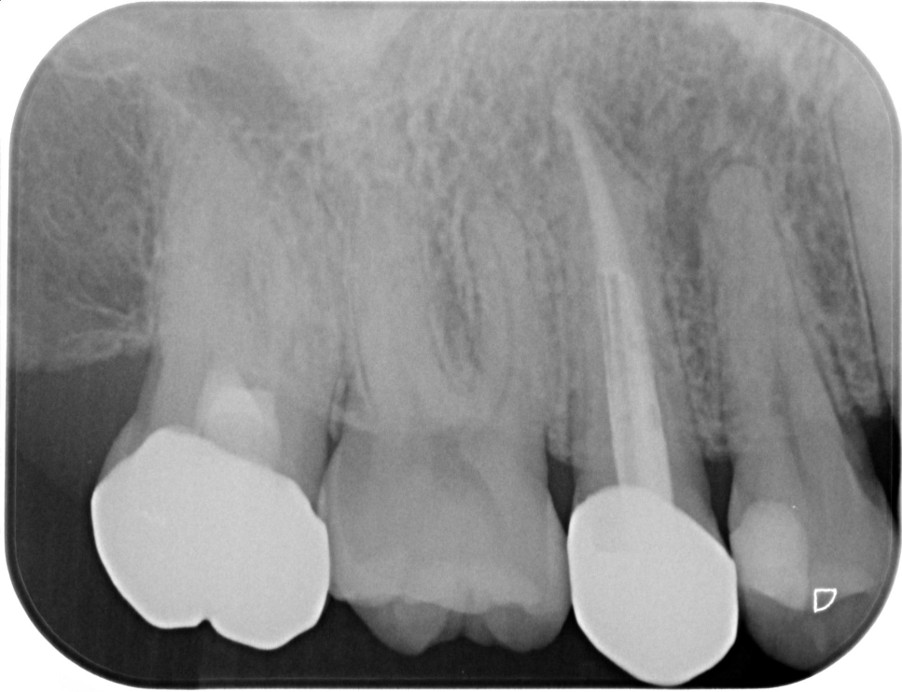

②![]() 根管治療後3か月経過 |

神経の治療後、①→②→③→④と時間をかけて徐々に治ってくることがあります。

神経の治療は細菌感染を除去する治療です。細菌がいなくなれば、無駄に神経をとらなくても良い歯もあるかもしれません。

| 患者様データ | 30代 男性 |

| 来院時の主訴 | 「他院で右上の歯3本とも神経をとる必要があると言われた。なんとか神経を残したい。」 |

| 術前検査結果 |

右上第一小臼歯:打診痛(+)・歯髄の生活反応有り 右上第二小臼歯:打診痛(+)・歯髄の生活反応無し 右上第二大臼歯:打診痛(ー)・歯髄の生活反応有り |

| 医院の診断 |

右上第一小臼歯:健全→術前に神経が残せる可能性のある歯と診断 右上第二小臼歯:慢性根尖性歯周炎→術前に神経が残せない歯と診断 右上第二大臼歯:無症候性可逆性歯髄炎→術前に神経が残せる可能性のある歯と診断し、術中に神経を残せると診断 |

| 通院期間 | 2年半 |

| 来院回数 | 10回(定期的なチェック含む) |

| 治療費 | 350,000円(税抜) 《内訳》 右上第二小臼歯:精密根管治療70,000円、ファイバーポストコア20,000円、セラミック治療120,000円 右上第二大臼歯:歯髄温存療法55,000円、セラミック治療85,000円 |

| リスクと副作用 | ①根管治療歯は長期的には破折するリスク ②メインテナンスが必要 |

| ココがこだわりのポイント☝ |

レントゲン検査や患者様の訴える症状だけでは神経を残せるかどうかは断定できません。 この方もレントゲン写真上では神経を残せないように見える歯でしたが、治療前に検査を入念に行うことで残せる可能性を見出すことができました。 同じ悩みを抱えた方は是非お気軽にご相談下さい。 |